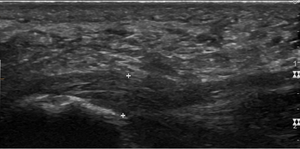

لفافة أخمصية سميكة تظهر في الموجات فوق الصوتية.

تحتوي اللفافة الأخمصية على ثلاث لفافات - اللفافة المركزية وهي الأثخن بسُمك 4 مم، واللفافة الجانبية بسُمك 2 مم، واللفافة الإنسية بسُمك أقل من 1 مم.[19] نظرياً، يصبح التهاب اللفافة الأخمصية أكثر احتمالًا مع زيادة سماكة اللفافة الأخمصية عند المدخل العقبي. قد يكون مفيداً في التشخيص التصوير بالموجات فوق الصوتية عند سمك يزيد عن 4.5 مم والتصوير بالرنين المغناطيسي عند سمك 4 مم.[20] نتائج التصوير الأخرى، مثل تحديد سماكة اللفافة الأخمصية، غير محددة ولها فائدة محدودة في تشخيص التهاب اللفافة الأخمصية.[13]